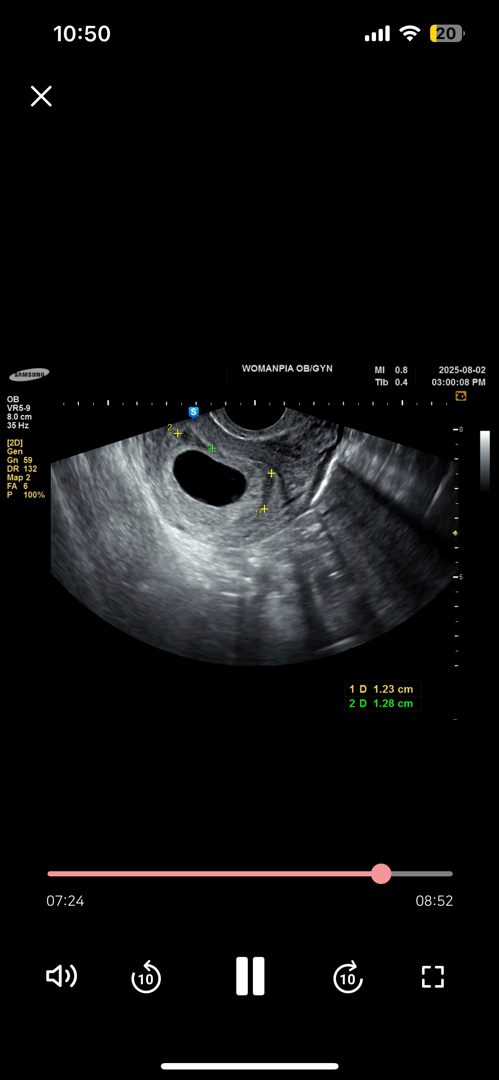

7주차 피고임 어때보이시나요

1.2cm 피고임 두개 보인다는데 따로 약을 주지도 누워만 있으라고 하지도 않았는데 걱정이되서요ㅠ 괜찮은건가요?